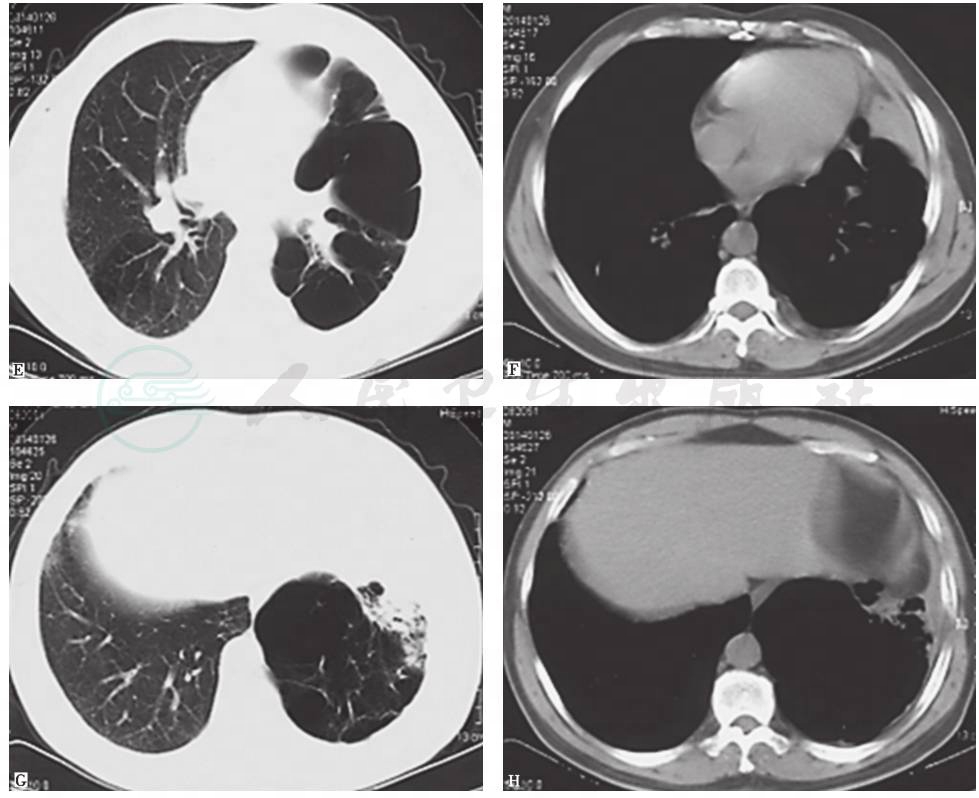

近13年来,患者胸部X线和CT均表现为左肺从初始体积大致正常,逐渐出现左肺体积减小,肺实质高密度影肺炎样改变;随着病情发展出现多发肺大疱、肺脓肿和肺毁损(图3~图10),并见左主支气管内病灶逐渐增大,最终导致管腔闭塞。

图7 6年半前胸部CT表现

胸部CT可见左主支气管被高密度钙化灶阻塞进一步加重,但左上肺体积增大含气增多,左下肺略缩小伴局限性斑片状高密度病灶和膨胀不全;右肺代偿性含气增多;左侧胸膜弥漫性病变减轻

图8 4年半前胸部CT表现

胸部CT可见左主支气管被高密度钙化灶阻塞进一步加重,管腔几近完全阻塞,左肺体积略缩小伴局限性不张,左上肺代偿性肺气肿和肺大疱进一步加重;右肺代偿性含气增多;未见左侧胸膜病变

图9 2年半前胸部CT表现

胸部CT可见左主支气管被高密度钙化灶管腔几近完全阻塞,左上肺代偿性肺气肿和肺大疱进一步加重,左下肺体积略增大伴多发肺大疱,并见左下肺前内基底段实变;右肺代偿性含气较前有所减轻

图10 1年前胸部CT表现

胸部CT可见左主支气管病灶同前,左上肺代偿性肺气肿和肺大疱进一步加重,左下肺多发肺大疱增多,左下肺前内基底段实变仍存在;右肺代偿性含气未见加重